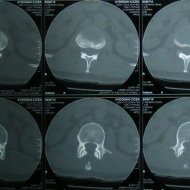

Omurga Kırığı

Omurga kırıkları osteoporozun olmadığı sağlıklı kişilerde trafik kazası ya da yüksekten düşme gibi yüksek enerjili travmalar sonucu oluşur. Eğer omurilik basısına neden olursa kısmi ya da tam felç ile sonuçlanabilir.

Eğer travma ilerleyen dönemde deformiteye yol açmayacaksa veya sinirlere baskı yaparak nörolojik bulguya neden olmadıysa korse ile tedavi edilebilir. Bu amaçla sert polietilen korseler ya da metalden yapılmış çerçeve tipi korseler kullanılabilir. Omurganın ağır zarar gördüğü durumlarda ileride oluşabilecek deformiteyi engellemek için omurganın vida ve çubuklarla sabitlenmesi gerekebilir. Nörolojik bulgu oluşturan bir kemiksel bası varsa, aynı seansta bu bası da ortadan kaldırılabilir.